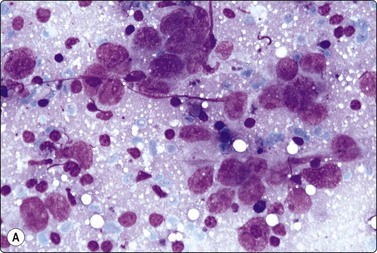

Fig. 4.7 Basaloid squamous cell carcinoma of head and neck

(A) Poorly differentiated cells with squamous features (MGG, HP; (B) Tissue section mimicking adenoid cystic carcinoma (H&E, IP).

Basaloid squamous carcinoma (Fig. 4.7) is a rare distinct variant of squamous cell carcinoma of the head and neck, which is clinically aggressive and has a predilection for the hypopharynx and the tongue. The smear findings are of squamous cell carcinoma without specific features, but a predominance of basal cells may make the distinction from the solid variant of adenoid cystic carcinoma difficult.43